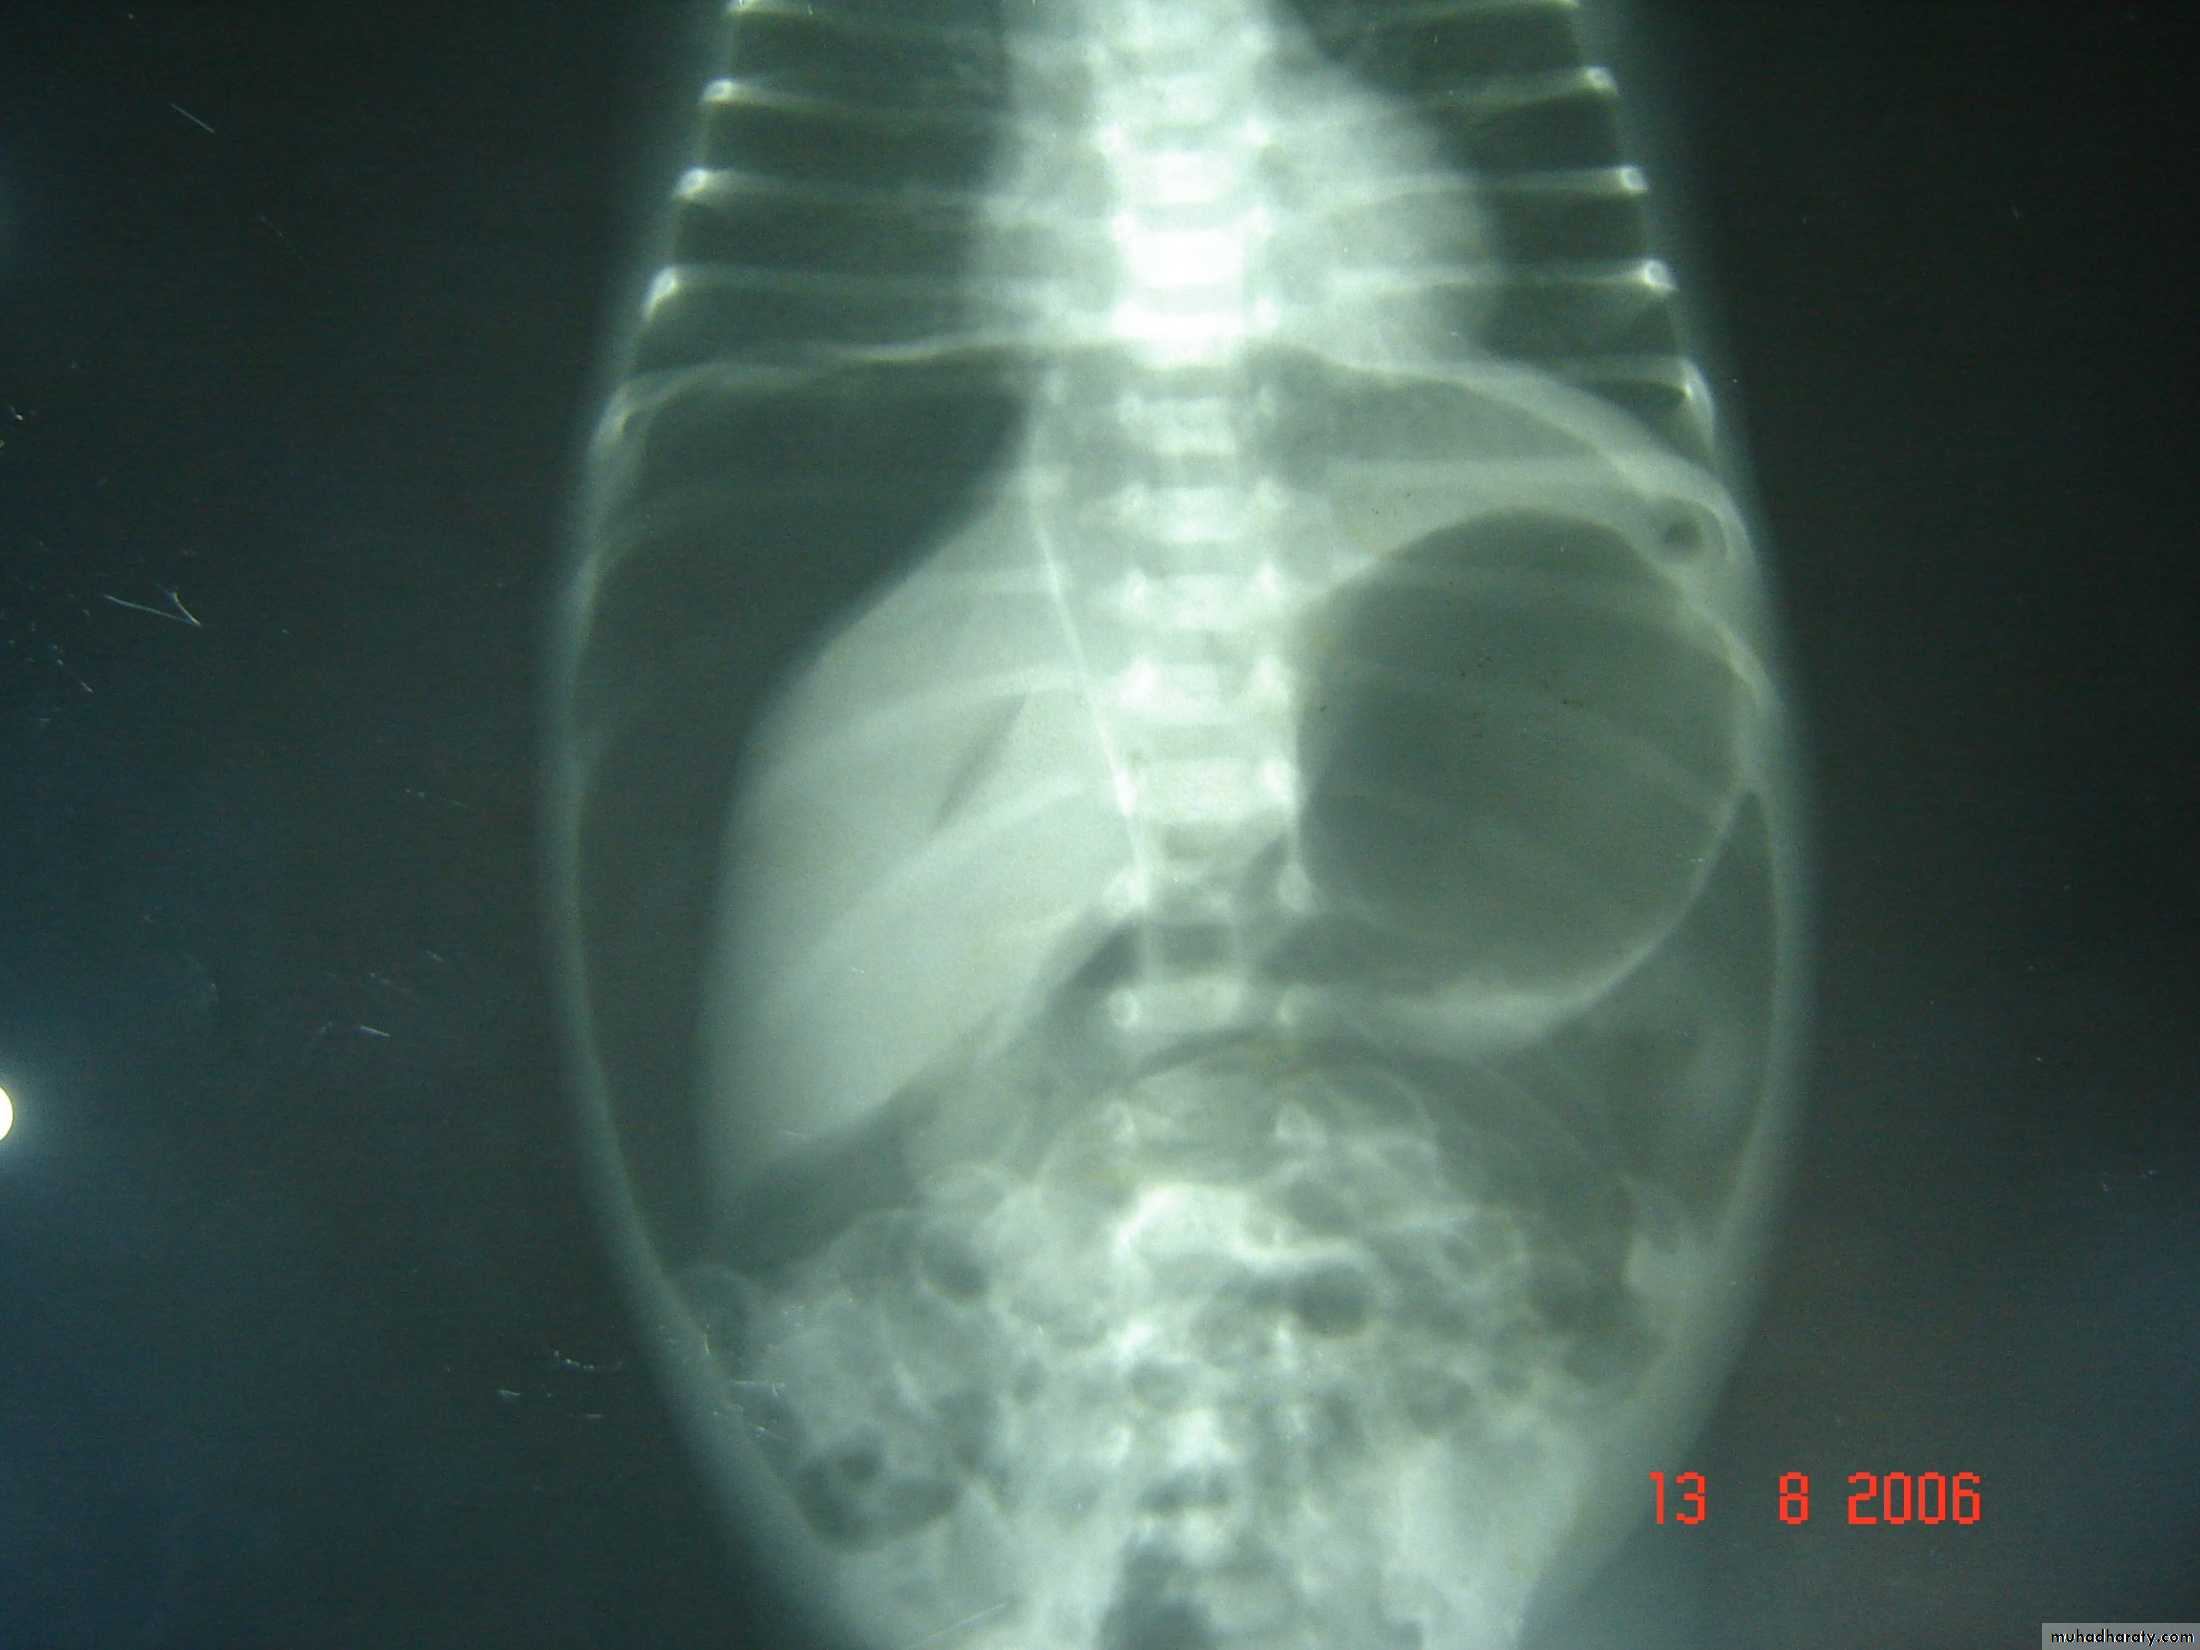

Respiratory Distress in the NewbornFirst photo:

Diagnosis: eventration of diaphragmDescription: mild dextrocardia – recurrent chest infection – diaphragm is present

mild distress - 7 months age baby – less number of intestinal loops in the chest

there is lung tissue in the chest - Paradoxical movement of the diaphragm.

Treatment: plication of the hemi-diaphragm (through thoracic approach).